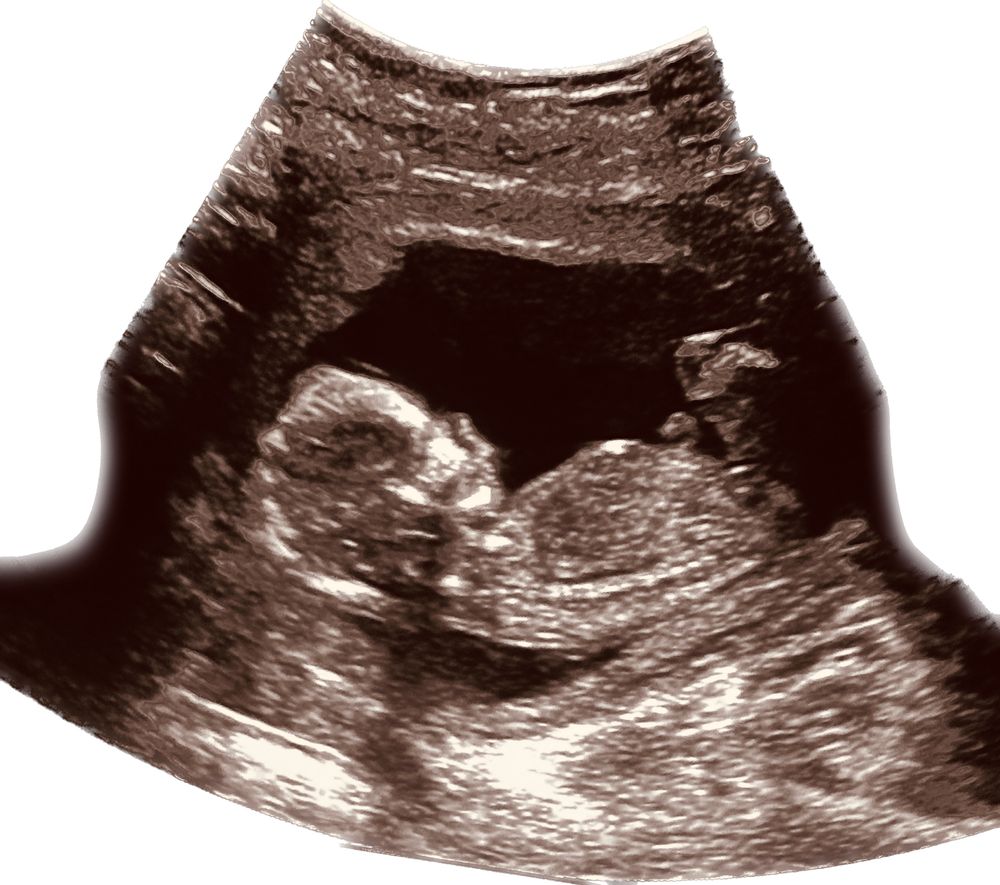

Классно! Помню Вашу историю! Какой пухляшик милый у Вас в животике возится!

Какой красавчик 😍 лёгкой Вам беременности и здорового малыша! У меня тоже хгч не сильно большой был (последний на 20 дпп 3500), по УЗИ и ктр на недельку отстаём от акушерского, но я верю в малыша и что догоним нужные параметры💪🏻 Ведь это такое счастье осознавать в себе новую жизнь ❤️

Какая прекрасная история🥰🥰🥰какой красивый малыш, растите и развивайтесь🥰🥰🥰 какая вы молодец что не отменили поддержку, и верили в своего малыша🤗🤗🤗